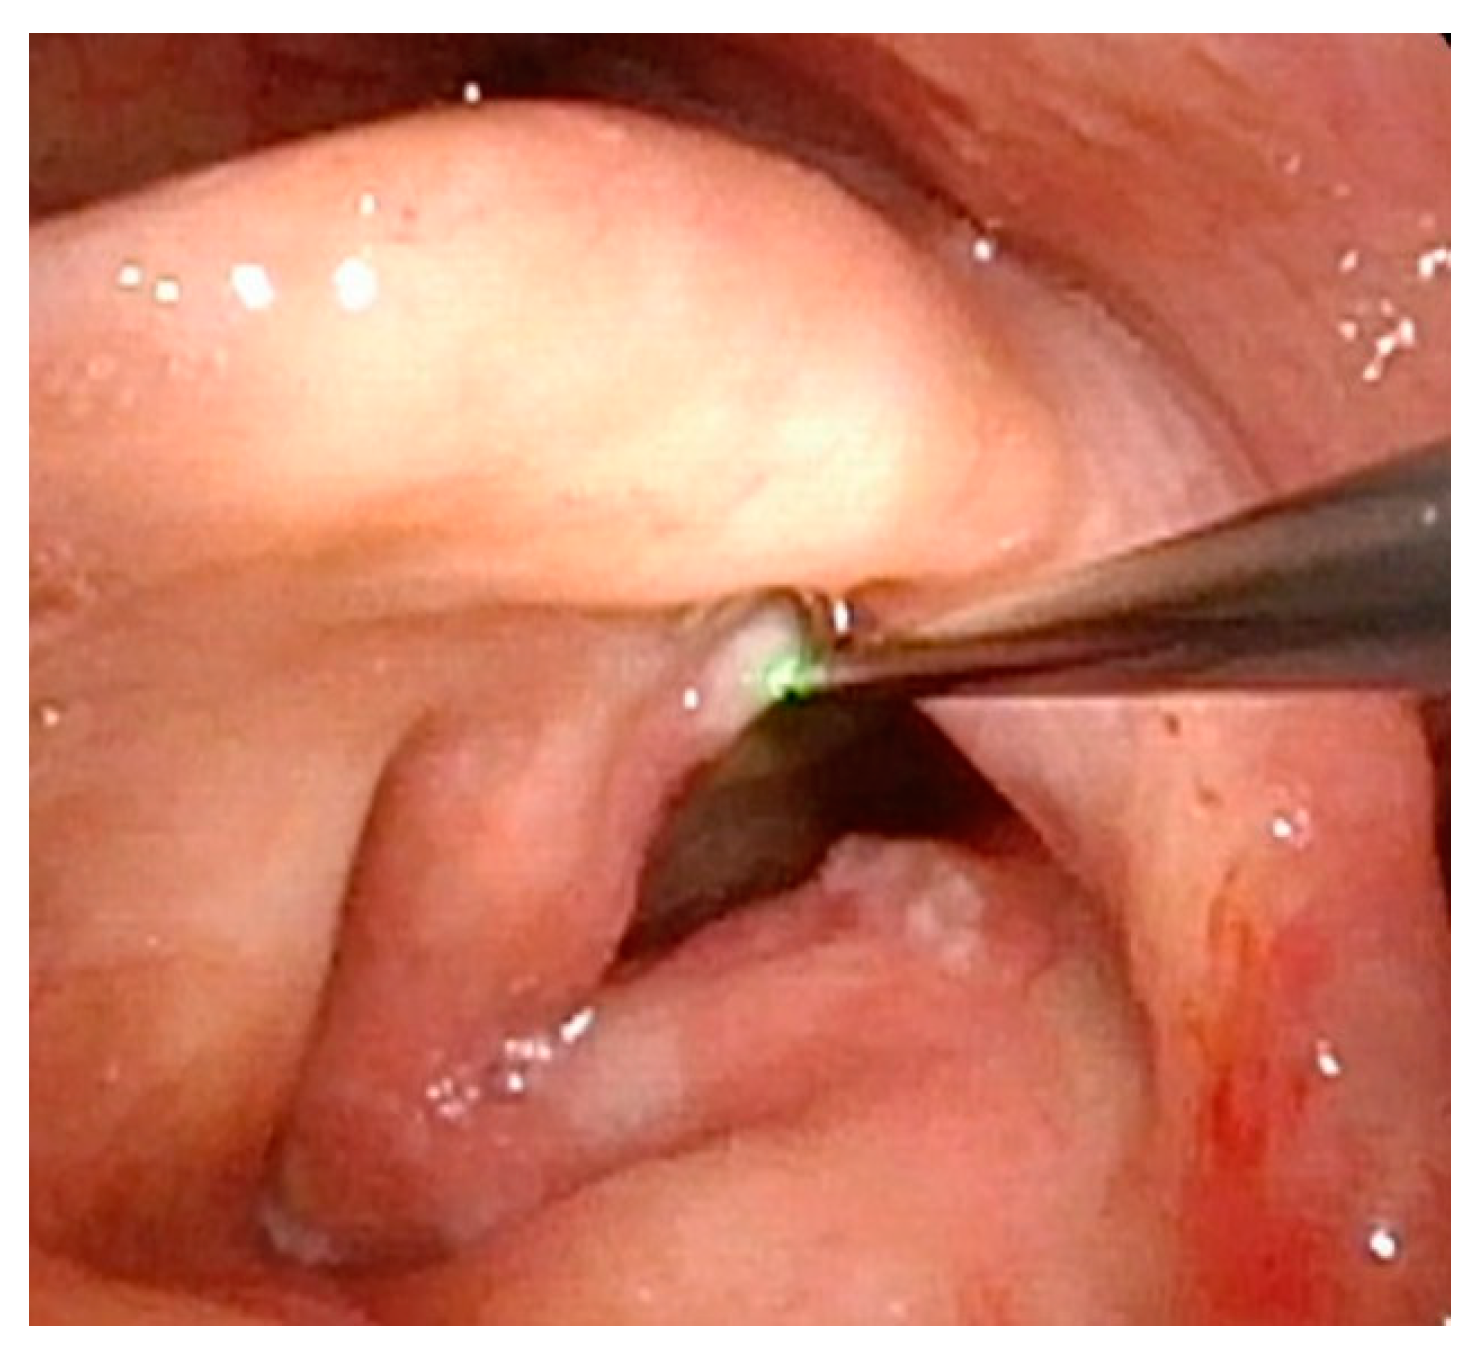

Management of LP has traditionally required surgical excision within the operating room. However, in more recent years, office-based procedures have provided an attractive alternative, with the goal of saving costs and time and avoiding the risks of general anesthesia (Figure 7 and Figure 8). Office-based laser therapy has been reported as a safe and effective treatment that is well tolerated in unsedated patients [53,54,55].

Figure 7.

Scattered papillomas through glottis with true blue laser beginning to ablate papilloma on the posterior right vocal fold.

Figure 8.

Completion of in-office laser treatment. Papillomas are either fully ablated or blanched white with the expectation of necrosis over the following week.